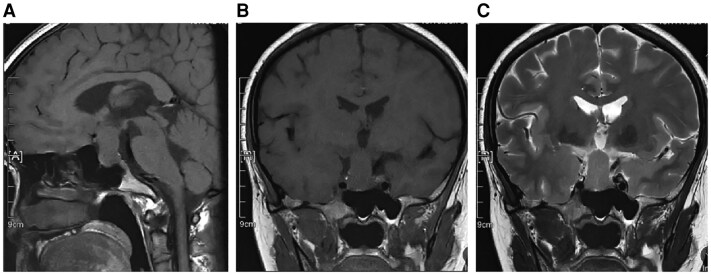

Pituicytomas are rare benign sellar tumors that originate in the neurohypophysis. We report the first case of a pituicytoma during pregnancy, causing headaches and bilateral temporal visual field defects. A 32-year-old woman at 16 weeks of gestation was admitted to our hospital for headaches and progressively worsening visual impairment. Cranial magnetic resonance imaging (MRI) revealed a sellar lesion that was resected via a neuroendoscopic endonasal-transsphenoid approach. Pathology revealed a pituicytoma with positive progesterone receptor expression. After cerebrospinal fluid (CSF) leakage repair and anti-infective therapy, the patient recovered well and finally gave birth to a healthy child. This is the first case of pituicytoma during pregnancy reported. Pregnancy may have a contributing effect on the progression of progesterone receptor-positive pituicytomas. Surgical intervention, when performed with appropriate perioperative management, can effectively alleviate mass effects caused by pituicytomas in pregnant women while maintaining the safety of the fetus.